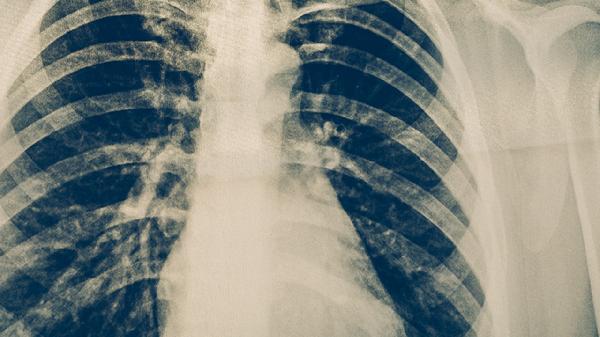

胸部X线能发现肺部结核病灶,典型表现为上肺野斑片状阴影、空洞形成等。该检查对活动性肺结核诊断价值较高,但早期病变可能漏诊,且存在辐射暴露风险。胸部X线异常需进一步做痰检确认。